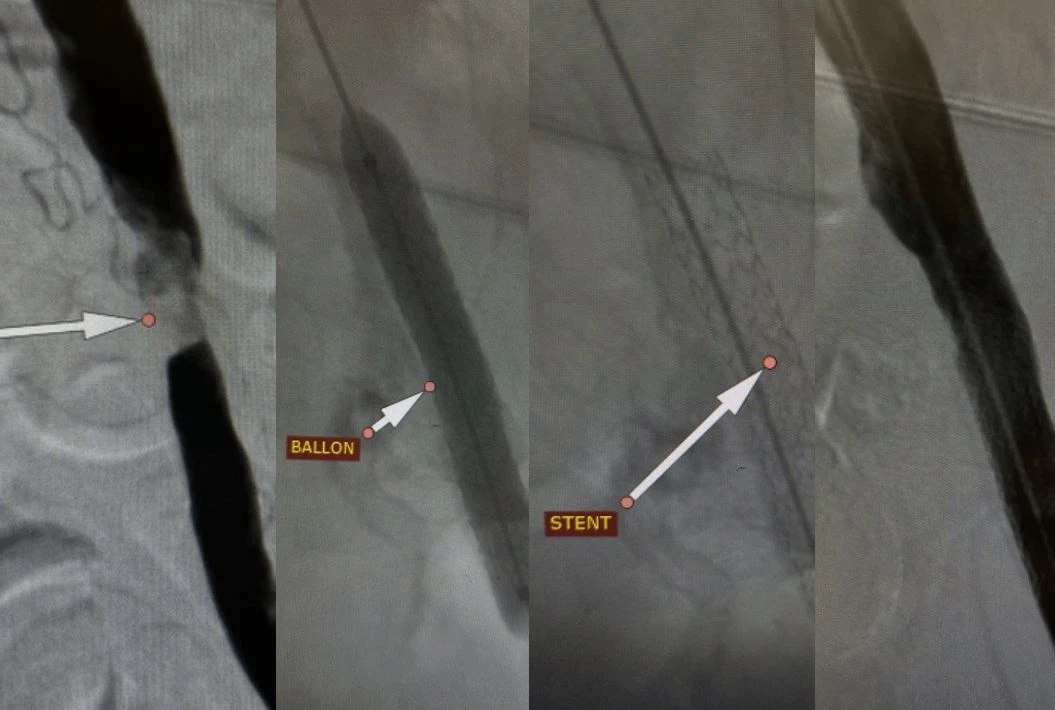

Через небольшой прокол в бедренной артерии врачи больницы №25 выполнили стентирование подвздошной артерии для поддержания просвета сосуда. Спустя сутки пациент смог самостоятельно передвигаться и покинул стационар, сообщает облздрав.